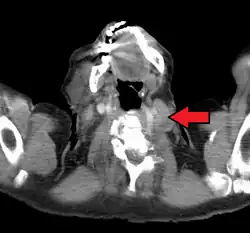

El nódulo de Virchow (también llamado nódulo de Troisier o nódulo de Virchow-Troisier )[1] es un ganglio linfático situado en la fosa supraclavicular izquierda (el área por encima de la clavícula izquierda). Recibe el drenaje de vasos linfáticos en la cavidad abdominal. El descubrimiento de un nódulo agrandado y endurecido ha sido largamente considerado como un fuerte indicativo de la presencia de cáncer en el abdomen, específicamente cáncer gástrico, que se ha expandido a través de los vasos linfáticos. Por esta misma razón a veces se lo llama nódulo señal o nódulo centinela. Pese a esto, el concepto no está directamente relacionado con el procedimiento del nódulo centinela que a veces se utiliza en cirugía oncológica, y tampoco tiene relación con la "glándula centinela" del epiplón mayor.

Los procesos malignos de los órganos internos pueden alcanzar un estado avanzado antes de dar síntomas. El cáncer gástrico, por ejemplo, puede permanecer asintomático mientras ocurre metástasis. Uno de los primeros puntos visibles donde estos tumores se propagan es el ganglio linfático supraclavicular izquierdo.

El ganglio supraclavicular izquierdo es el nódulo de Virchow clásico porque es en el lado izquierdo del cuello donde el drenaje linfático de casi todo el cuerpo (a través del conducto torácico) ingresa a la circulación venosa por medio de la vena subclavia izquierda. La metástasis bloquea el conducto torácico, provocando regurgitación a los ganglios circundantes, como el nódulo de Virchow. Otro concepto es que uno de los ganglios supraclaviculares corresponde al ganglio final a lo largo del conducto torácico y por esto se da el agrandamiento.[4]

El diagnóstico diferencial de un nódulo de Virchow agrandado incluye linfoma, varios procesos malignos intraabdominales, cáncer de mama e infección (por ejemplo del brazo). De forma similar, un ganglio linfático supraclavicular derecho agrandado tiende a drenar procesos malignos torácicos tales como cáncer de pulmón y de esófago, al igual que linfoma de Hodgkin.